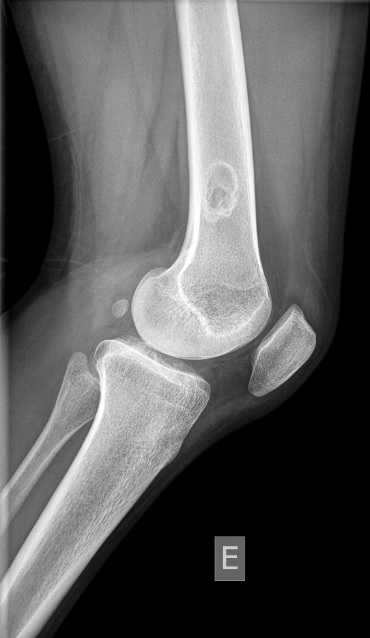

A 6-week-old male infant was brought to the emergency department with a three-day history of irritability, decreased food intake and a polymorphic skin eruption. He had no significant medical history, was exclusively breastfed with good weight gain. None of his family members had similar symptoms or lesions. The infant was in good general condition. Skin examination revealed an erythematous base with scattered vesicles, pustules and papules. The lesions were more prominent on the scalp, back and abdomen, including the neck, inguinal and axillary regions (Figure 1). Blood parameters were within reference ranges for age, with no increased inflammatory markers. Nevertheless, due to the exuberance of the lesions, a bacterial infection was suspected and intravenous flucloxacillin was initiated.

The following day, the infant presented with new lesions and nodular scabies was suspected. The delta-wing jet sign observed on direct dermoscopy confirmed the diagnosis (Figure 2). The patient and his parents were treated with topical 6% sulfur ointment for three consecutive days, repeated after seven days.

Figure 1A and 1B. Lesions in the torso: scattered vesicles, pustules, papules and nodules in an erythematous base.